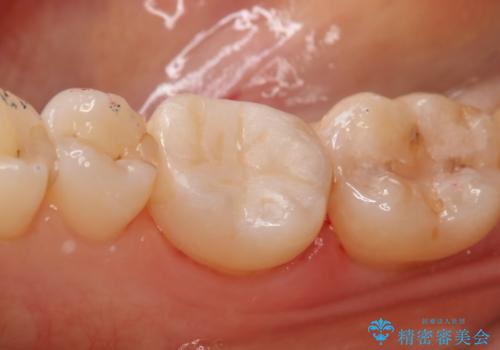

銀の詰め物が取れた セラミックインレー治療

- 右下6番のメタルインレー脱離のため来院。

セラミックの治療を希望されたため切削量を考慮し、セラミックインレーでの治療を選択しました。

う蝕が深くまで進行していたので、CRで裏層した上で形成・印象をしています。